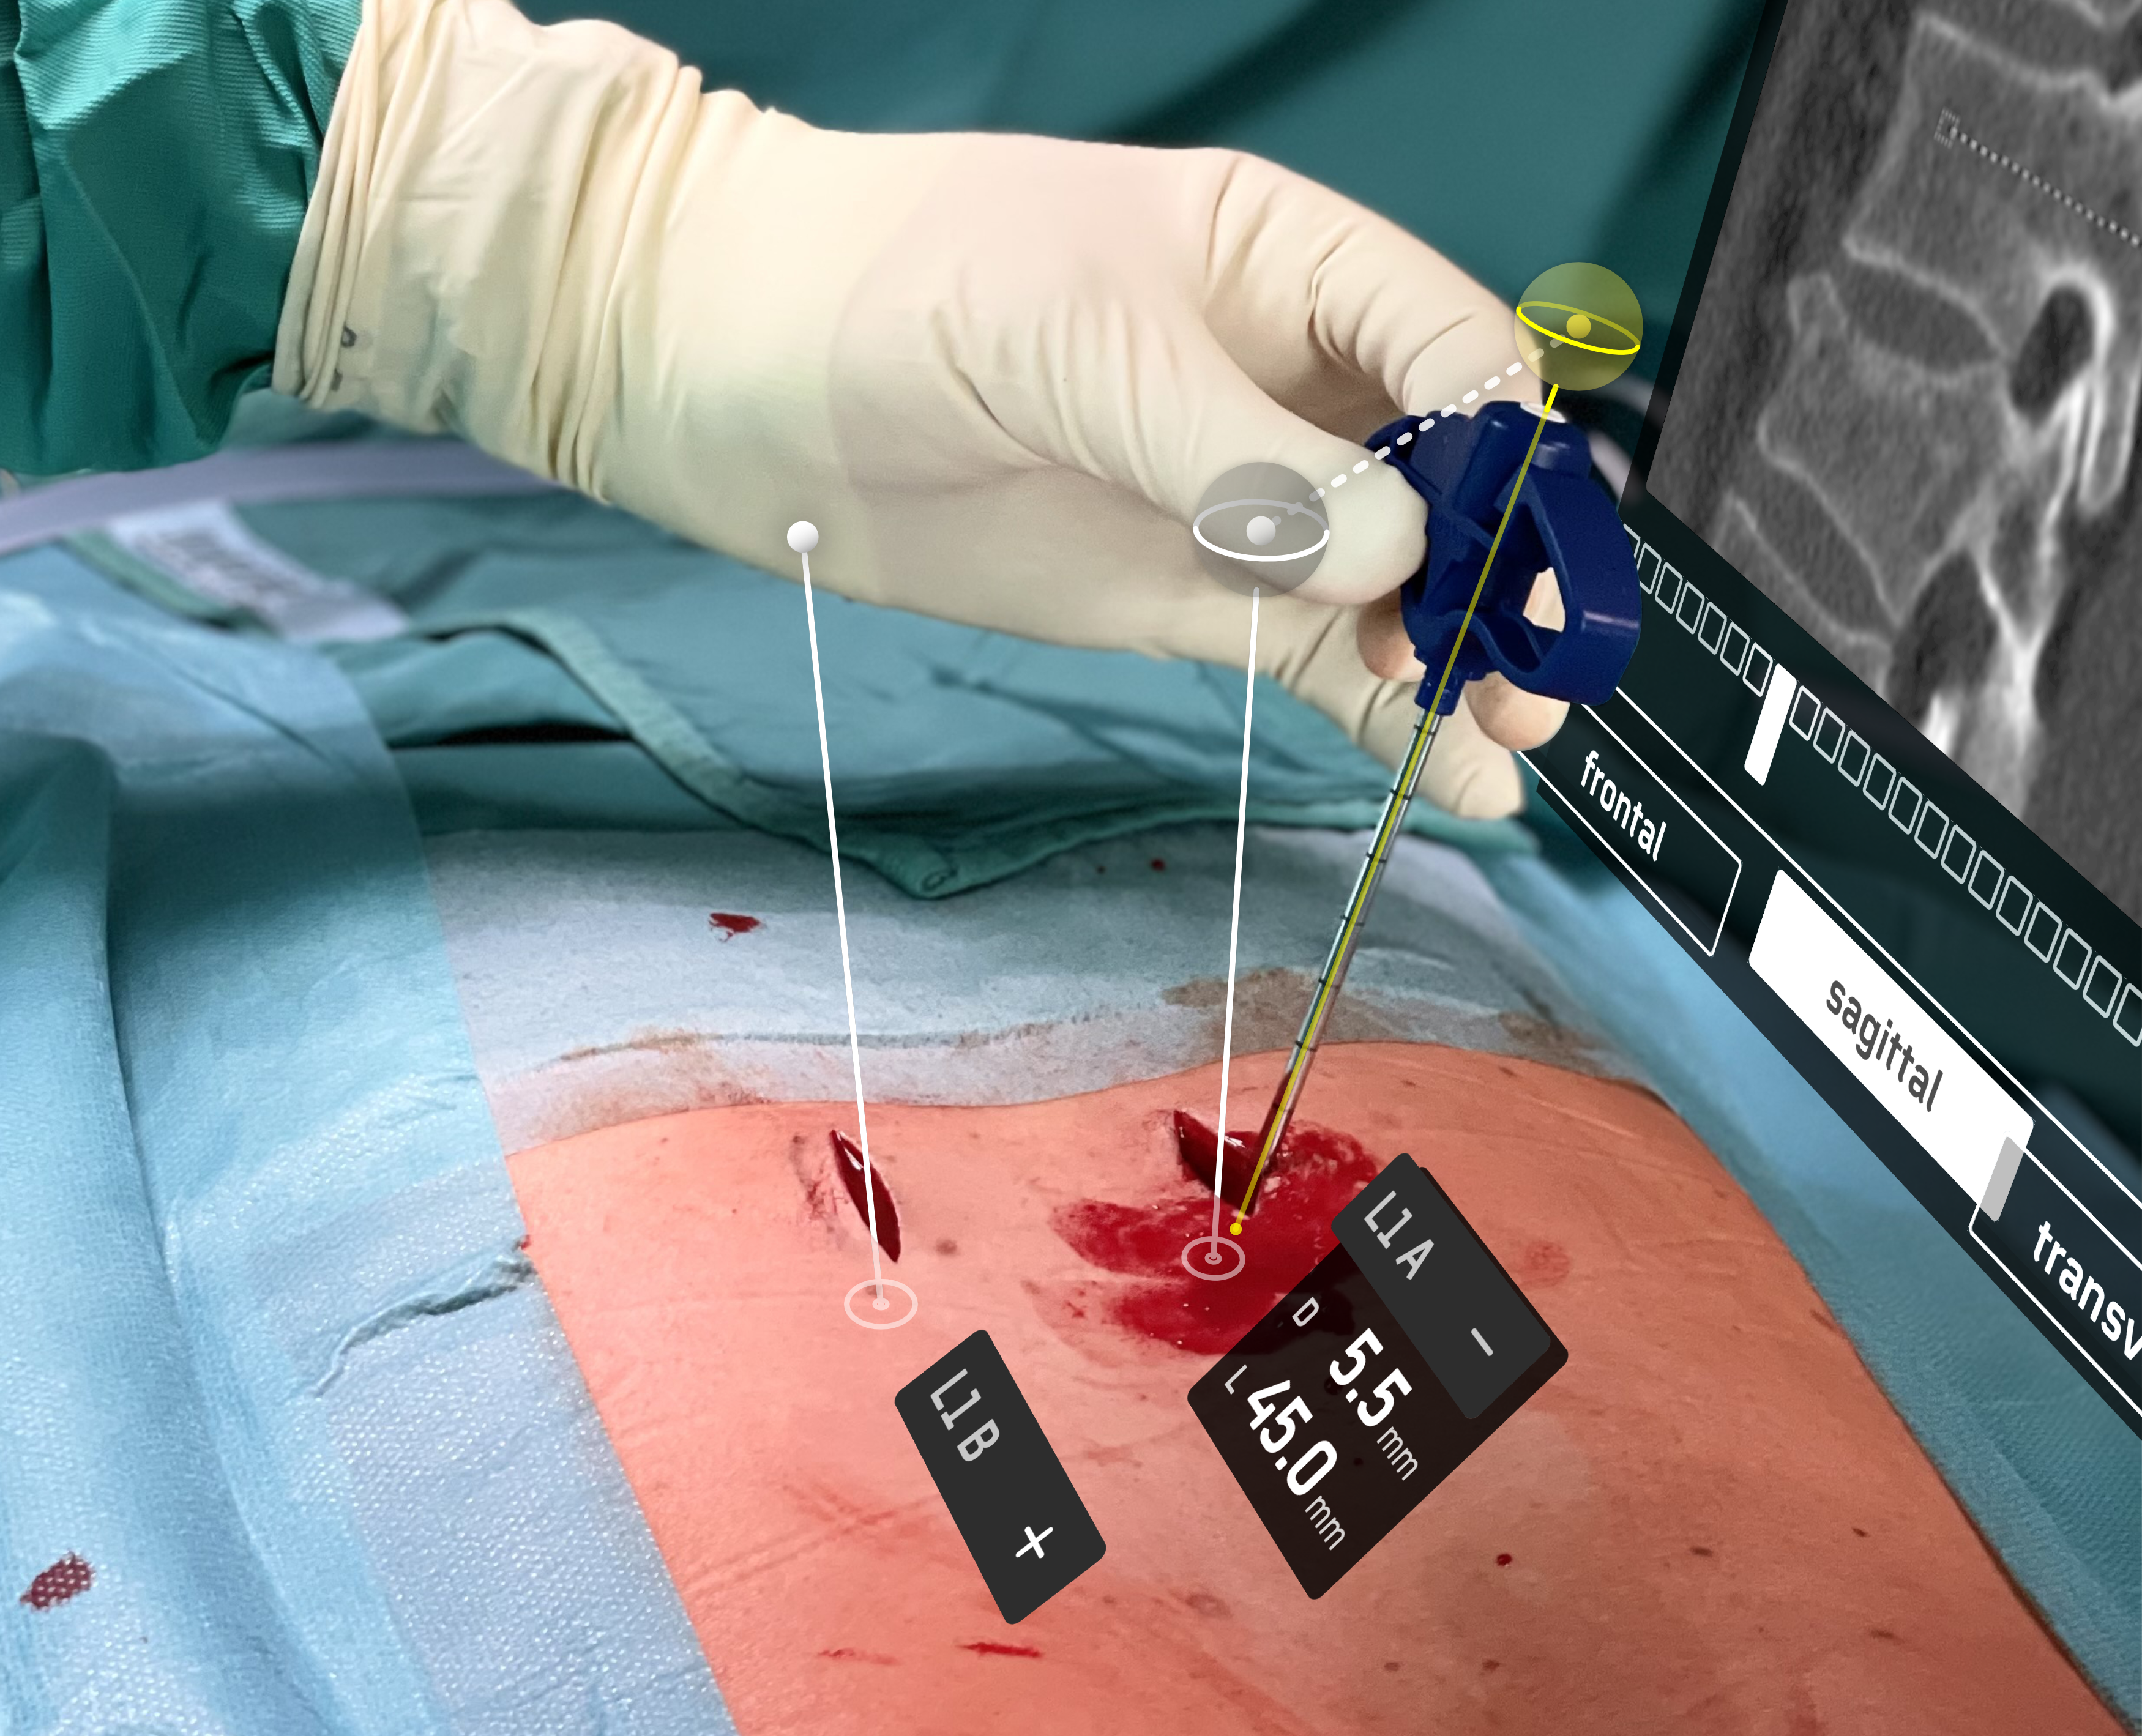

Surgical practice usually separates between imaging and intervention: i.e. a surgeon has to apply a CT scan to the patient's anatomy cognitively. With spatial and embodied computing we seek to bring digital and physical environments into one big picture. In a series of case studies we explore how new sensing, imaging and display technologies create new opportunities for surgical practice and education. In order to create such an mixed reality (#MR) we collaborate with disciplines such as game design, computer science, media studies and engineering in order to shape the next generation of human machine cooperation.

Pogorzhelskiy, Queisner, Remde, Sauer (CC BY-NC-ND)